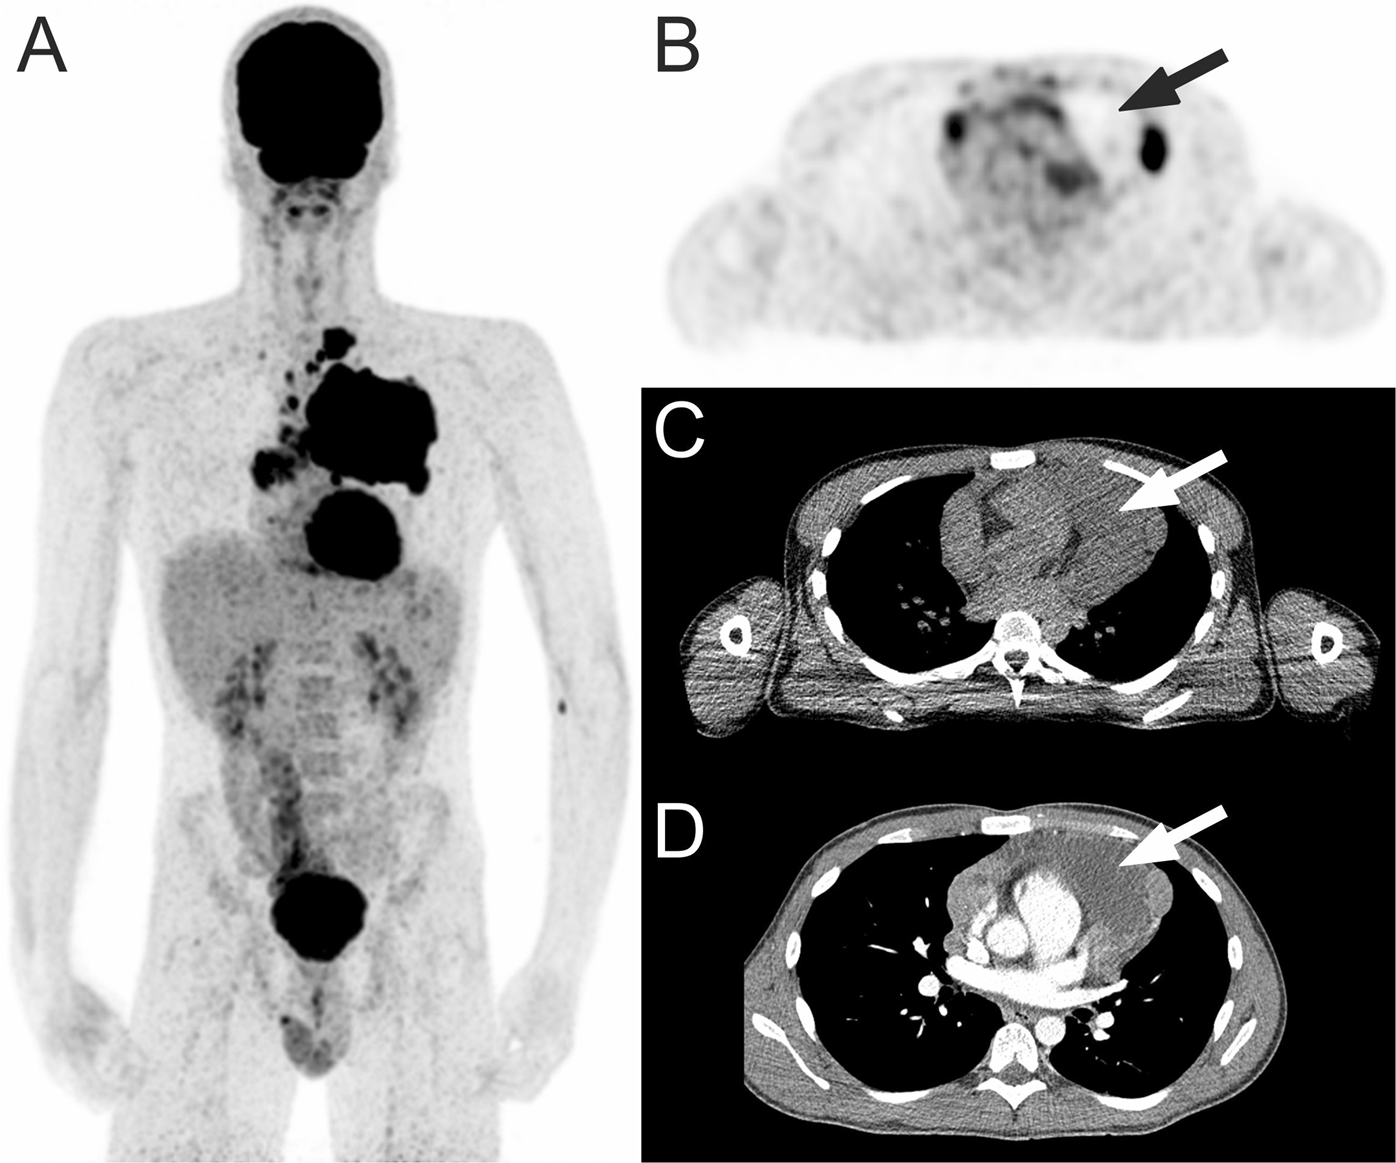

Figure 2

18F-FDG PET in a 21-year-old man with classical Hodgkin lymphoma. Coronal maximum intensity projection 18F-FDG PET shows a mediastinal tumor mass (A). Axial 18F-FDG PET with concomitant low-dose CT shows necrosisvisual with a photopenic area in the mediastinal tumor (B,C, arrows), with attenuation of around 18 HU on contrast-enhanced CT (D, arrow).